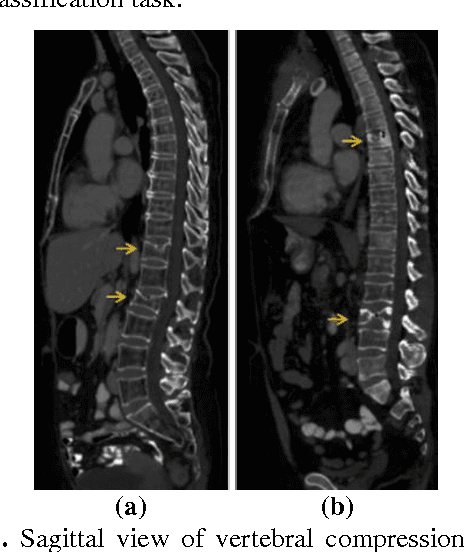

Abstract:Classification of vertebral compression fractures (VCF) having osteoporotic or neoplastic origin is fundamental to the planning of treatment. We developed a fracture classification system by acquiring quantitative morphologic and bone density determinants of fracture progression through the use of automated measurements from longitudinal studies. A total of 250 CT studies were acquired for the task, each having previously identified VCFs with osteoporosis or neoplasm. Thirty-six features or each identified VCF were computed and classified using a committee of support vector machines. Ten-fold cross validation on 695 identified fractured vertebrae showed classification accuracies of 0.812, 0.665, and 0.820 for the measured, longitudinal, and combined feature sets respectively.

Abstract:The precise and accurate segmentation of the vertebral column is essential in the diagnosis and treatment of various orthopedic, neurological, and oncological traumas and pathologies. Segmentation is especially challenging in the presence of pathology such as vertebral compression fractures. In this paper, we propose a method to produce segmentations for osteoporotic compression fractured vertebrae by applying a multi-atlas joint label fusion technique for clinical CT images. A total of 170 thoracic and lumbar vertebrae were evaluated using atlases from five patients with varying degrees of spinal degeneration. In an osteoporotic cohort of bundled atlases, registration provided an average Dice coefficient and mean absolute surface distance of 2.7$\pm$4.5% and 0.32$\pm$0.13mm for osteoporotic vertebrae, respectively, and 90.9$\pm$3.0% and 0.36$\pm$0.11mm for compression fractured vertebrae.